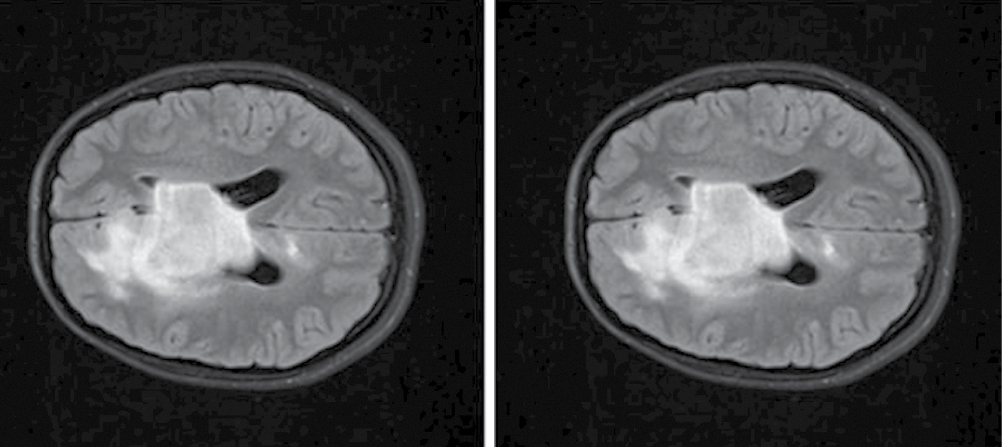

Let us compare these image preprocessing techniques. The ScaleIntensity transform is meant to uniformly increase the brightness of an image by adjusting the values of all its voxels. As a rule, the voxel values are scaled to the predefined value range by applying the linear transformation. For example, the ScaleIntensity transform can scale voxel values, which were initially in the range of 0–255, to a predefined range, often improving the quality of image interpretation without significant change of voxel-to-voxel ratio. In other words, ScaleIntensity allows us to augment the brightness of the image, preserving the texture of dark and light areas (Fig. 6). Uniform adjustment mitigates the risk of information loss due to critically excessive voxel intensity values.

Fig. 6. Diffuse glioma (Т2-FLAIR, ах).

А — raw data; В — ScaleIntensity transformed data.

This method also helps denoise MR images and facilitates the image structure interpretation by avoiding artifacts, which may appear with more aggressive contrast adjustment. In comparative analysis, ScaleIntensity brings a certain consistency to images with different noise levels, which is crucial for scientific imaging data analysis4. In turn, contrast adjustment modifies the difference between the darkest and brightest parts of the image by expanding or shrinking the range of voxel values, which improves visibility within the range by making dim areas darker and bright areas brighter. While AdjustContrast can help improve blurred image details and textures, it can also cause the risk of the detail loss in the clipping areas with too bright or dark colors. Unlike ScaleIntensity, which transforms all voxels uniformly, AdjustContrast improves the image non-uniformly by highlighting certain areas while shadowing texture in other areas, which may complicate the interpretation of the image5.